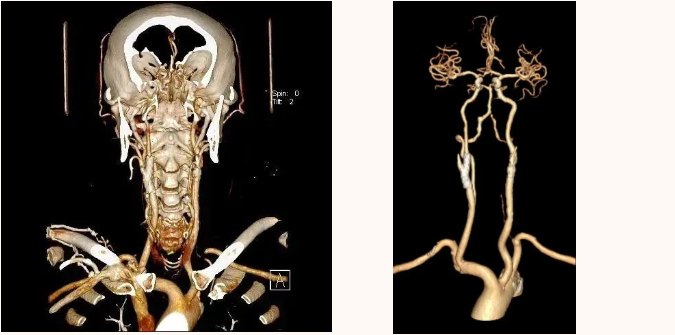

CT 血管造影(CTA),即 CT 血管成像,是一种利用计算机三维重建方法合成的非创伤性血管成像技术,可以在没有创伤的情况下,很好地了解身体中血管的情况。具有时间短、无创、特异性和敏感性高,时间和空间分辨率高等特点,能全方位显示出血管病灶,对于经其他检查已经明确患有血管疾病,需进一步了解病情严重程度具有重要的意义。

通过 CT 血管成像,可显示动脉病变,如血管闭塞、动脉瘤及夹层动脉瘤、血管畸形、血管损伤、心脏冠状动脉病变等。可进行冠心病 CT 筛查,冠心病术前、术后评估,脑卒中一站式检查,灌注成像等。

CT 血管造影(CTA)检查适用于动脉夹层、动脉瘤、不明原因出血、缺血性疾病、血管畸形、动脉栓塞、动脉硬化、动脉变异等血管疾病。

CTA 检查在大血管、外周血管疾病、心脏冠状动脉相关疾病、中枢神经系统疾病以及肿瘤疾病的诊断中发挥着重要作用。